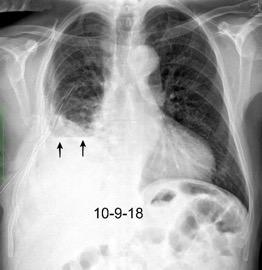

Derrame pleural 43-48% de pacientes con embolismo.

< 1/3 de hemitórax: 90%.(puede haber en lado opuesto).

Siempre exudados.

75% de los pacientes con TEP y derrame pleural tienen dolor pleurítico.

La disnea desproporcionada

Tromboembolismo pulmonar.

Frecuencia del derrame:

Rx: 32%. TC: 47%

Unilateral. 85%

< 1/3 del hemitórax: 90%

Todos exudados

58% con eritrocitos

21% tabicación lo que causa demora en el diagnóstico